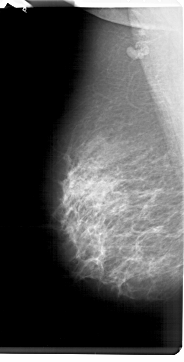

A_1298_1.RIGHT_MLO

RIGHT_MLO LINES 6871 PIXELS_PER_LINE 3346 BITS_PER_PIXEL 12 RESOLUTION 43.5 OVERLAY